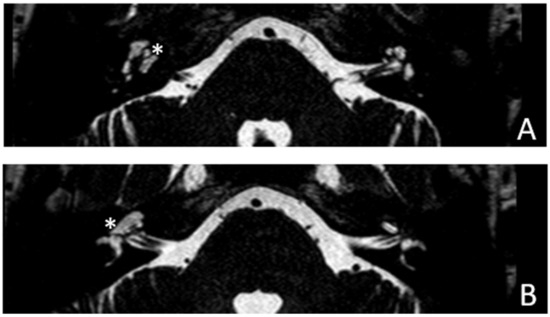

Figure 6. MR images of patient #3 with otosclerosis and SSC dehiscence on the left side. MR cisternography: (A,B), axial plane. Note the fluid-signal in the newly formed cavity (white asterisk).

Figure 8. MR images of patient #4 with otosclerosis. MR cisternography, axial plane. Note the fluid signal in the newly formed cavity (white asterisks).